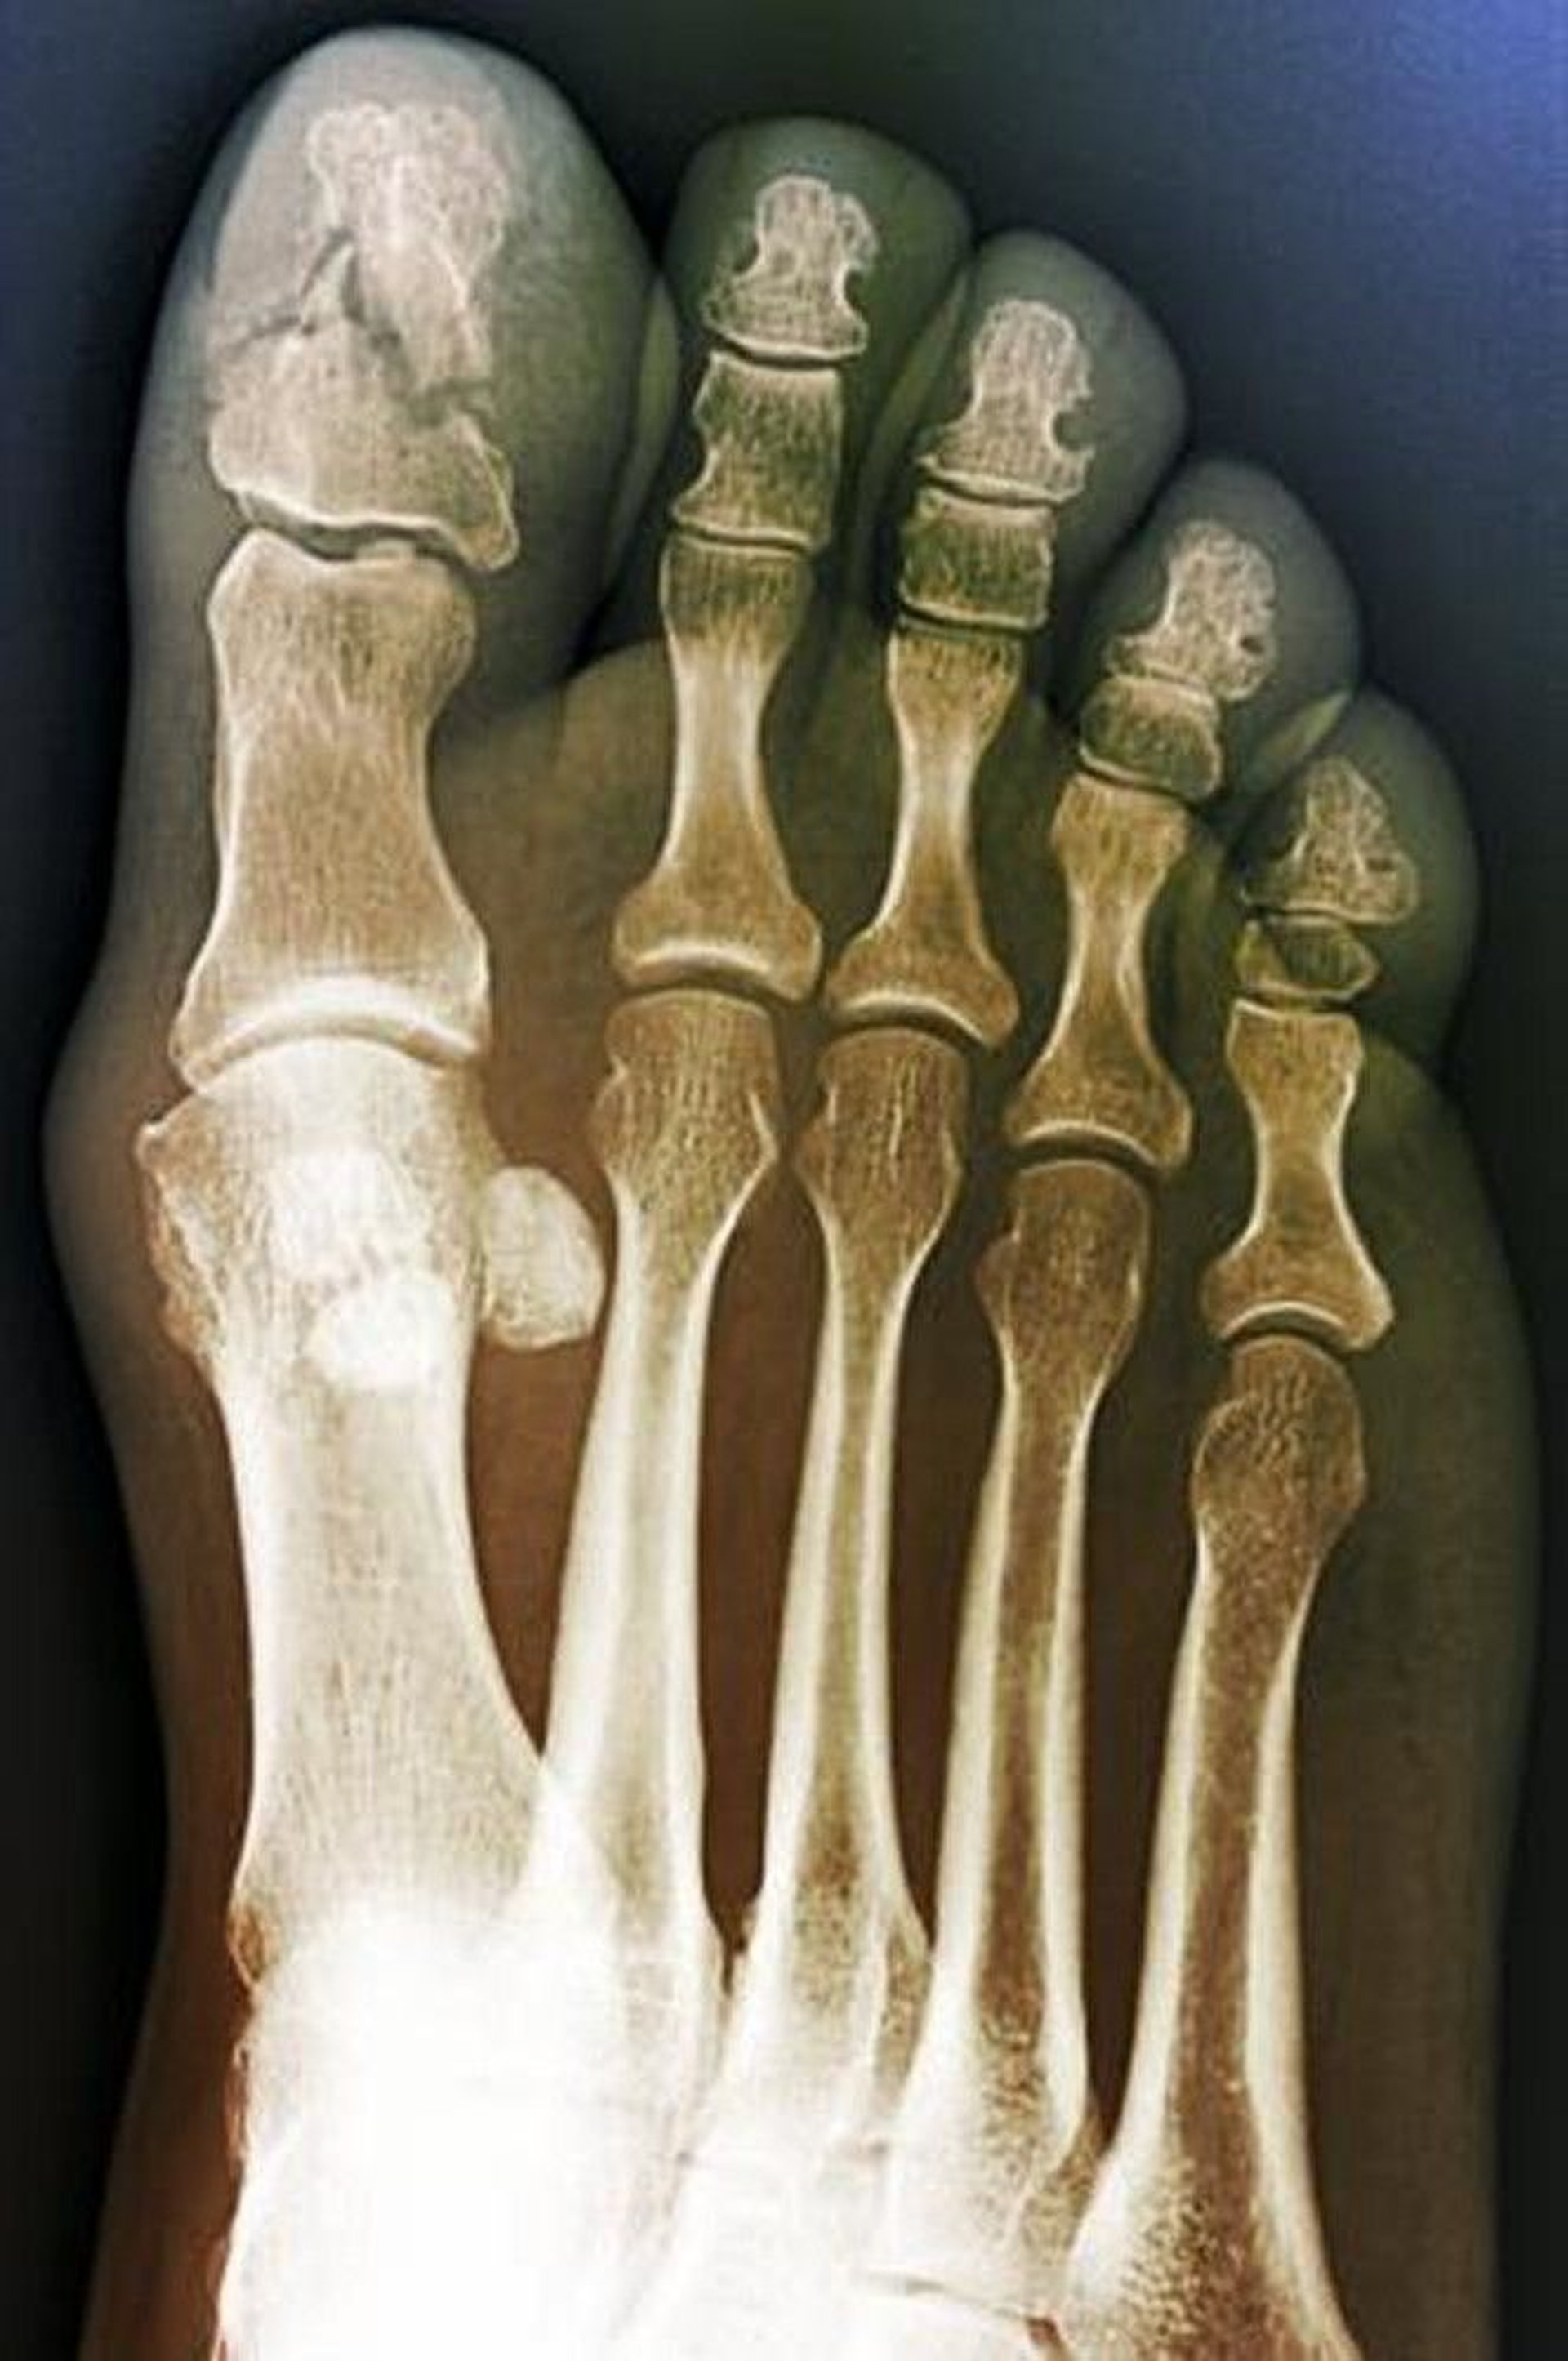

Comminuted Fracture of the Great Toe

This anteroposterior view shows a comminuted fracture of the great toe distal phalanx. This finding suggests a crush mechanism.